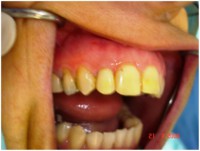

Carga Imediata após exodontia atraumática

Fatos interessantes pertinentes a este caso:

- Extração imediata

- Implante imediato

- Carga imediata

- Coroa protética cerâmica imediata